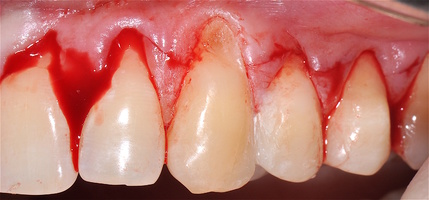

7. Этапы хирургического лечения рецессий десны на верхней челюсти

Второй сегмент был прооперирован через 4 месяца после операций на нижней челюсти, область операции включила в себя зубы от 2.1 до 2.6.

В области 2.3 зуба глубина рецессии составила 6 мм (2-й класс по Миллеру), кератинизированная десна отсутствует, толщина слизистой — 0,7 мм. Это показание к применению аутотрансплантата(свободного десневого деэпителизированного трансплантата) именно в области 2.3 зуба. Донорская зона позволила сделать забор аутотрансплантата размером 15 мм, которого хватило на общую ширину рецессий двух зубов: 2.3 и 2.4.

При устранении рецессий десны коронально-смещенным лоскутом по De Sanctis M. и Zucchelli G. в остальных участках был использован пластический материал аллогенного происхождения — ТМО (dura mater).

Хирургический протокол операции соответствовал технике коронально-ротированного смещения, пласти- ческий материал и аутотрансплантат были полностью перекрыты слизисто-надкостничным лоскутом и зафиксированы швами. Обработка поверхностей корней зубов проводилась аналогично.

Первый сегмент был прооперирован через 2,5 месяца после операции во втором сегменте.

В области 1.3 и 1.2 зубов выявлены рецессии десны глубиной 6 мм 2-го класса, полное отсутствие прикре- пленной десны, толщина ее составила 0,6 мм. Зона хирургического устранения рецессий от 1.6 до 1.1 зубов.

Протокол операции коронально-ротированного лоскута по методике M. De Sanctis и G. Zucchelli: дизайн разрезов с измерением глубины рецессий, отслаивание слизисто-надкостничного лоскута и его мобилизация.

Деэпителизация анатомических сосочков, обработка поверхностей корней зубов, фиксация свободного десневого аутотрансплантата и пластического материала ТМО (dura mater) швами, с полным перекрытием слизисто-надкостничным лоскутом, фиксация швами слизисто-надкостничного лоскута узловыми одиночными швами в области установки аутотрансплантата и ТМО (dura mater), двойными обвивными для слизисто-надкостничного лоскута, и крестообразными прижимающими горизонтальными швами для фиксации слизисто-надкостничного лоскута в новом положении. Обработка поверхностей корней зубов проводилась аналогично.

Послеоперационный период после всех операций протекал спокойно, без воспаления и особенностей, реактивный отек соответствовал норме в случае применения аутотрансплантата и ТМО (dura mater).

Реактивность в области применения ТМО и аутотрансплантата была сопоставима и сравнима с травмой мягких тканей при хирургическом вмешательстве. Имеет место реакция в обоих случаях на операцию, но на материал ТМО реакция отсутствует.